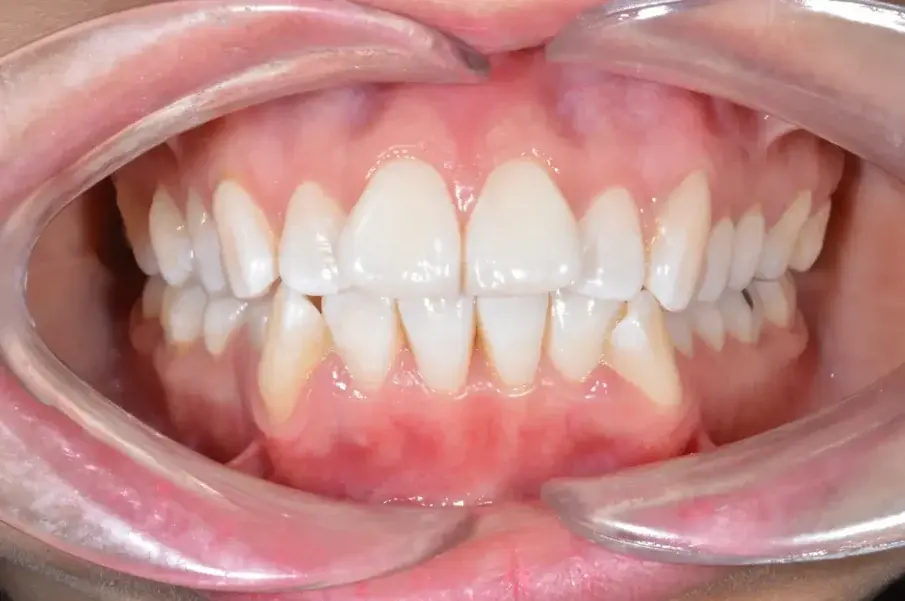

С ортодонтското лечение беше постигната дистализация на предните зъби чрез използване на максимална опора на долната челюст и умерена на горната челюст (фиг. 5–7). В края на лечението беше постигната стабилна двустранна оклузия от клас I, както и нормално наклоняване и ретрузия на предните зъби, което доведе до подобряване на профила (фиг. 8–10).

Фиг. 7а: Окончателни интраорални снимки.

Фиг. 7b: Окончателни интраорални снимки.

Фиг. 7c: Окончателни интраорални снимки.

Фиг. 7d: Окончателни интраорални снимки.